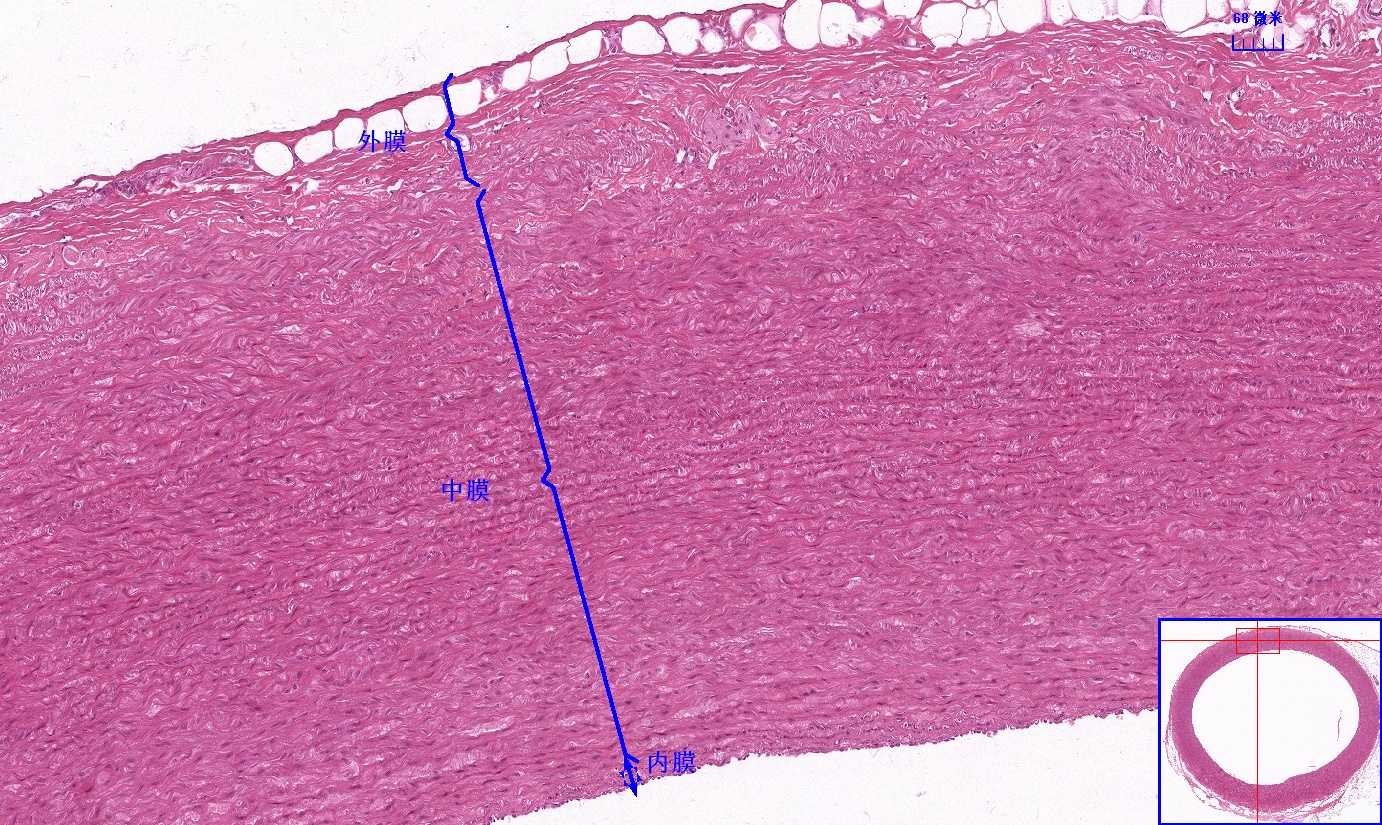

6 第六单元 循环系统

6.1 循环系统切片库

6.2 循环系统微课

6.3 循环系统课件